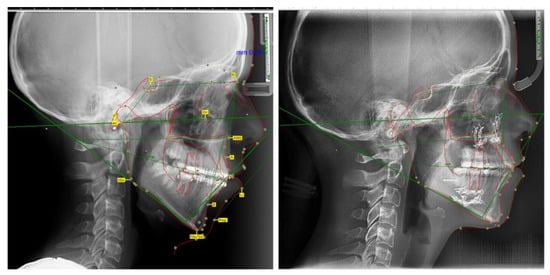

| Parameters | Normal Values | Pre- Treatment | Before Orthognatic Surgery | After Orthognatic Surgery | Differences |

|---|---|---|---|---|---|

| FMA | 25 ± 3° | 39.22° | 36.13° | 28.23° | 10.99° |

| IMPA | 88 ± 3° | 98.03° | 93.22° | 91.14° | 6.89° |

| SNA | 82 ± 2° | 78.32° | 78.17° | 80.35° | −2.03° |

| SNB | 80 ± 2° | 73.98° | 74.12° | 78.22° | −4.24° |

| IF | 107° ± 5° | 120.85° | 107.32° | 111.80° | 9.05° |

| HFP/HFA | 0.69 | 0.52 | 0.54 | 0.64 | 0.12 |

| Upper lip length (mm) | 23.4 ± 3.42 | 14.5 | 14.7 | 16.8 | 2.3 |

| FMI | 81.9 | 111.6 | 110.2 | 84.3 | 27.3 |

| U1-SN | 103 ± 7° | 115.12° | 104.78° | 109.50° | 5.62° |